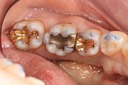

Ted Kanamori #29, 30, 31 pre-op

Ted Kanamori #29, 31 caries removal